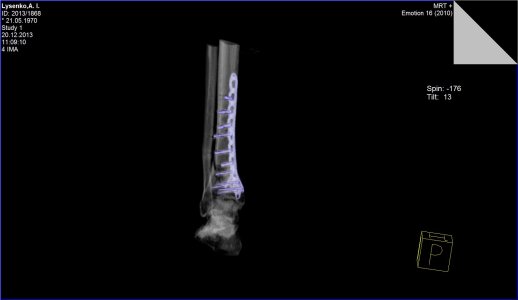

Здравствуйте. Меня зовут Андрей, мне 43 года. 5 сентября этого года меня травмировало на работе - перелом малой и большой берцовой кости со смещением. Операцию сделали 25 сентября, поставили пластину и наложили гипс. Через месяц врач-травмотолог гипс разрешил снять, но сказал, что нагрузку на ногу давать ещё рано. Очередное СКТ, которое я сделал 20 декабря показало, что кость до сих-пор не срослась. В настоящее время я всё-ещё хожу на костылях. Скажите пожалуйста имеет-ли вообще подобный перелом возможность срастись и если да, то сколько времени это может занять. Мой врач ни каких прогнозов дать пока не может и к сожалению ни какой информации мне по этому поводу не дает.